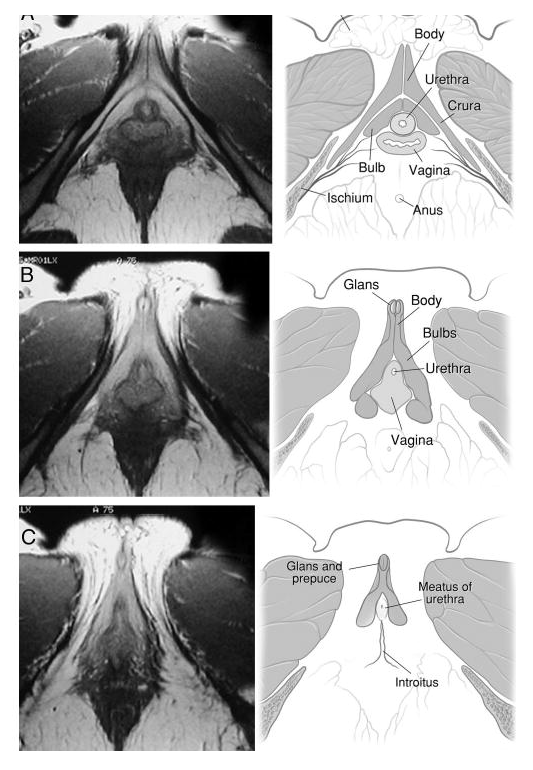

- Voici l'une des recherches du docteur Helen O'Connell, celle qui a tout réexaminé à l'IRM. Un petit aperçu :

Lien